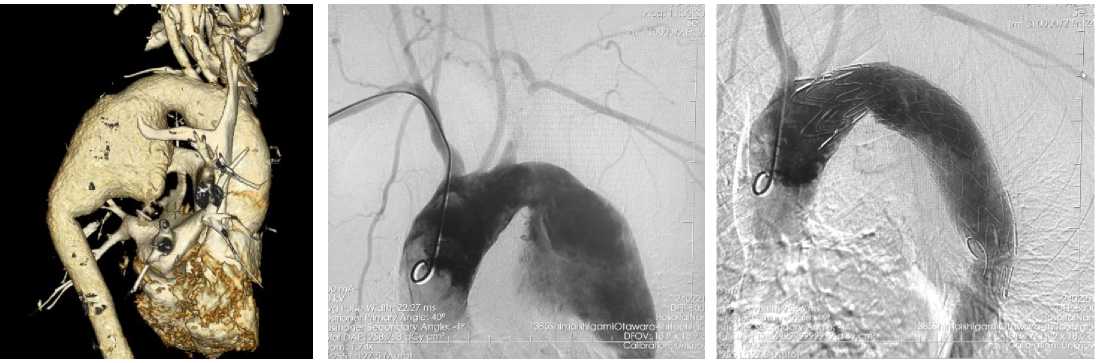

Время пережатия левой ОСА – 20 минут.

Вторым этапом выполнено эндопротезирование аорты (рис. 1, 2). Катетер для инвазивного измерения артериального давления в левой лучевой артерии. В правой лучевой артерии установлен интро-дьюсер 6F. Мобилизирована правая общая бедренная артерия (ОБА), произведена пункция правой ОБА, установлен интродьюсер 6F, выполнена катетеризация восходящего отдела грудной аорты. Через трансрадиальный интродьюсер по проводнику заведён катетер Pigtail в восходящий отдел аорты. Выполнена ангиография грудного отдела аорты, визуализирована аневризма нисходящего отдела грудной аорты. По диагностическому катетеру в восходящий отдел аорты поведён проводник Lunderquist. Стент-графт Ankura TAA3428B180 позиционирован и имплантирован в нисходящий отдел грудной аорты ниже отхождения левой ОСА. Выполнена контрольная ангиография, стент полностью расправлен, эндолик под протезом отсутствует, брахиоцефальный ствол, левая ОСА и сонноподключичный анастомоз проходимы, свободно контрастируются.

Рисунок 2. Данные интраоперационной ангиографии

Figure 2. Intraoperative angiography data

Рисунок 1. Данные 3D-реконструкции

Figure 1. 3D reconstruction data